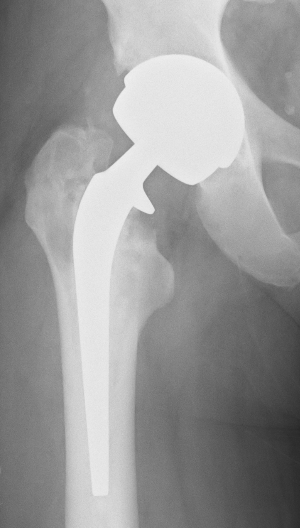

We reviewed my X-rays and confirmed the osteolysis and bone loss. The health of the bone at the top of the femur is a concern and I am going to have a nuclear medicine bone scan tomorrow morning to see what is going on with the blood flow to and around the bone.

The movement of the prosthesis, or lines suggesting movement within the femur where obvious (it seems?).

So – bottom line, for whatever reasons, this hip is not performing and so the surgeon is intending to remove it in a few weeks and put a lovely Smith & Nephew Ceramic on Ceramic hip in its place.

It is going to the a biggish operation as the press-fit acetabular cup will have to come out and a bone graft will be required to fit the new cup plus a few trusty screws..

And then he will need to dig out the femoral implant but the way it looks that should come out very easily – but he will then have to dig out the old cement and the cement that spewed down the femur when the last surgeon did not use a glue cup.

A longer femoral stem will be required and he may get away with a press fit – time will tell.